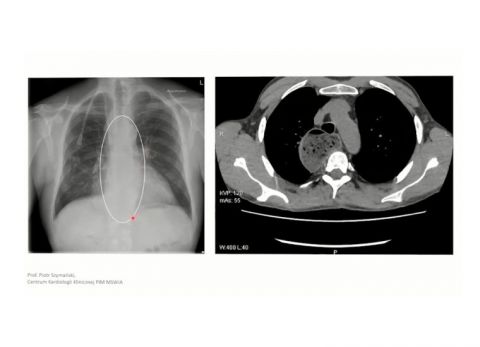

Wideo Echokardiografia. Przypadek 44

Prof. dr hab. n med. Piotr SzymańskiPacjentka z niewydolnością nerek